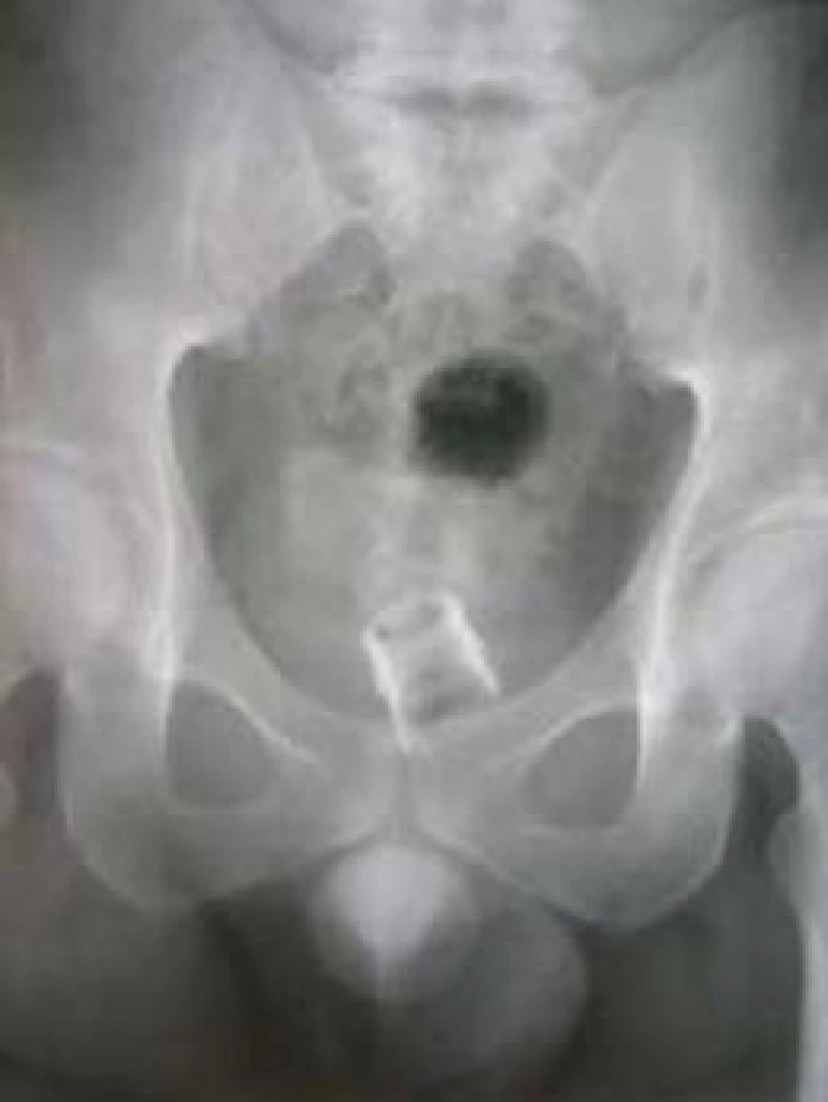

Фото 1НемедицинаFigure 1. Рентгеновский снимок, показывающий фрагмент бутылки в прямой кишке Немедицина